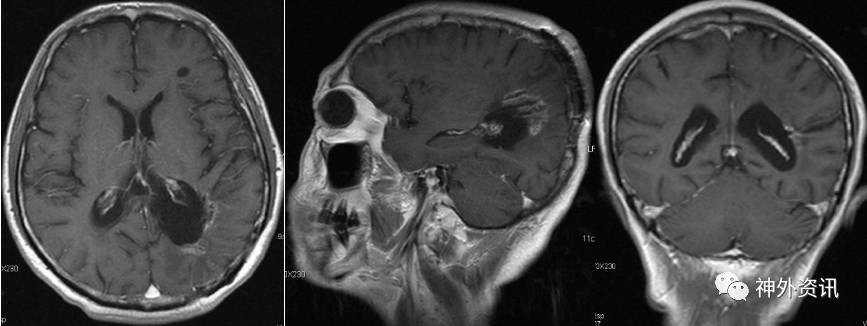

辅助检查:增强MRI示(2016.7.12):左侧顶枕骨术后改变,左侧脑室后角旁不规则形异常信号,大小约37mm*46mm*39mm,呈T1、T2等信号,内见小片T2稍高信号,增强后呈明显强化,强化尚均匀,周边见大片T1低信号、T2高信号水肿区,左侧颞叶及右侧脑室后角旁见小片类似强化信号,左侧侧脑室受压,双侧脑室前后角旁及半卵圆中心、左侧额叶见多发点片状长T2高信号。影像诊断:左侧顶枕骨术后改变,左侧脑室后角旁旁、左侧颞叶、右侧脑室后角旁淋巴瘤复发。两侧脑室前后角旁及半卵圆中心多发缺血灶。左侧额叶囊性病变(图3)。血化验未见明显异常。浅表淋巴结超声、胸片、心电图等相关检查均未见明显异常。

图3. MRI检查:左侧脑室后角旁不规则形异常信号,大小约37mm*46mm*39mm,呈T1、T2等信号,增强后呈明显强化,强化尚均匀,周边见大片T1低信号、T2高信号水肿区。